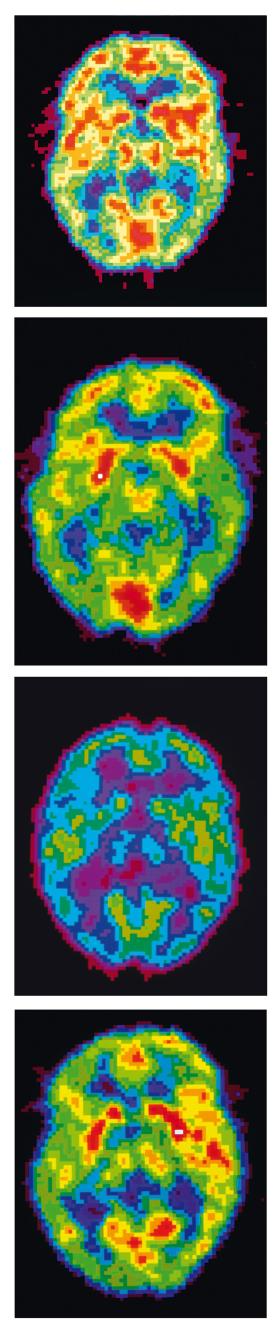

Obrazowanie mózgu w fazie (od góry): REM, wybudzenia, głęboki sen, sen normalny.Science Photo Library/East News Obrazowanie mózgu w fazie (od góry): REM, wybudzenia, głęboki sen, sen normalny.